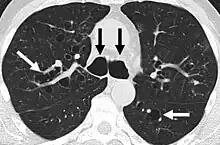

A chest x-ray is abnormal in most patients with bronchiectasis. Computed tomography is recommended to confirm the diagnosis and is also used to describe the distribution and grade the severity of the disease. Radiographic findings include airway dilation, bronchial wall thickening, and atelectasis.[3]

Bronchiectasis primarily in the middle lobe of the right lung.

Bronchiectasis secondary to a large carcinoid tumor (not shown) that was completely obstructing the bronchus proximally. Dilation of the airways is present.